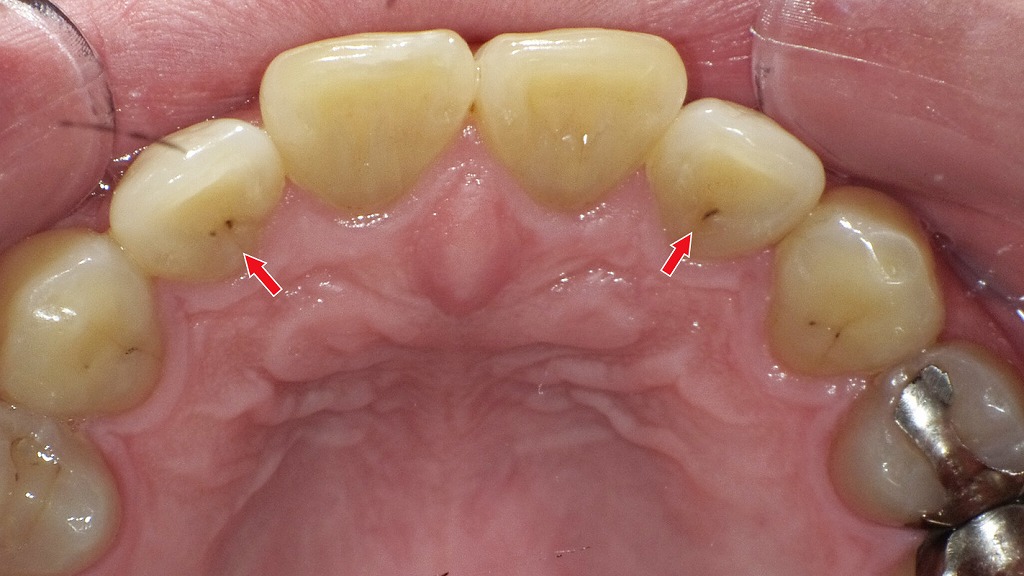

赤矢印が示すように、歯と歯の間(コンタクト部)の初期虫歯は、肉眼ではほとんど確認できません。レントゲンを撮影することで、エナメル質内部の透過像として虫歯を早期に発見できます。見た目に穴がなくても進行している場合があるため、定期的なレントゲン検査は非常に有効です。